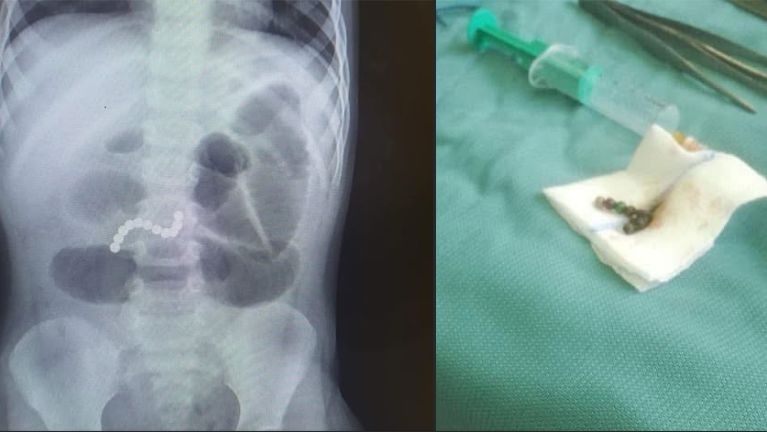

Z pozoru niewinna zabawka stała się przyczyną dramatycznej walki o zdrowie dziecka. 6-letni chłopiec trafił na Szpitalny Oddział Ratunkowy z silnym bólem brzucha. Początkowo objawy sugerowały zwykłą infekcję żołądkowo-jelitową. Dopiero badanie RTG ujawniło szokującą prawdę – dziecko połknęło magnetyczne kulki, które w jego wnętrzu zaczęły działać jak pułapka.

Magnetyczne kulki, popularne wśród dzieci jako gadżety do zabawy lub układania wzorów, potrafią być skrajnie niebezpieczne, gdy dostaną się do przewodu pokarmowego.

Szczególnie groźne jest połknięcie więcej niż jednej kulki – wówczas potrafią one przyciągnąć się przez ściany jelit, powodując ich zgniecenie, niedrożność, a nawet perforację, czyli rozerwanie.

Tak było w przypadku 6-letniego pacjenta, który wymagał pilnej operacji. Tego typu sytuacje niestety nie są rzadkością. Lekarze z oddziałów ratunkowych alarmują: to codzienność na SOR-ach i w chirurgii dziecięcej.